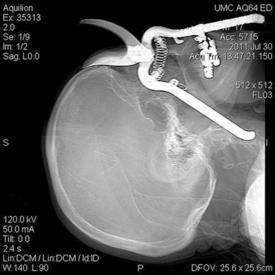

A man aged 50 years arrived at the ED with abdominal pain that had begun after eating steak at a backyard barbeque. Computed tomography (CT) scan of the abdomen and pelvis revealed a linear object extending through the wall of a loop of small intestine into the omentum (Figure). Laparotomy was performed to remove the foreign body, which appeared to be a wire bristle from a grill-cleaning brush. The patient fully recovered and was discharged the next day.

Five more patients visited the ED during August 2011–June 2012 after inadvertent ingestion of a wire bristle that had become dislodged from a grill-cleaning brush and embedded in food. In all of the cases, the bristles were initially identified by radiographs of the neck or CT scans of the abdomen and pelvis, and their origin was confirmed after removal (Table). Patient interviews revealed a common history of recent ingestion of grilled meat. After definitive treatment, all six patients recovered fully.

Severe abdominal pain was the chief symptom of the other patients, who were three men aged 31, 35, and 50 years (Table). These patients were evaluated primarily with intravenous contrast-enhanced CT of the abdomen and pelvis. In two patients, the wire bristle was noted lodged within the omentum adjacent to a loop of small intestine. In one patient, the wire bristle was located within the sigmoid colon, indenting the bladder. Two patients underwent emergency abdominal surgery to retrieve the foreign object and repair the intestine. In one patient, the wire had not perforated the intestine and was removed via colonoscopy.